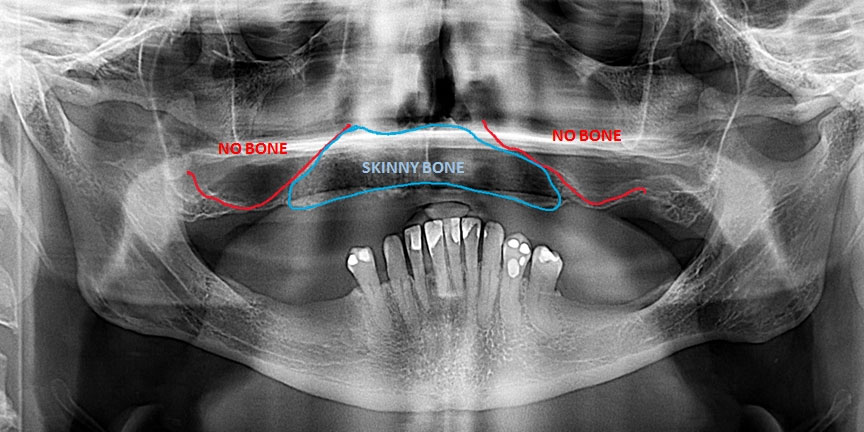

Expertise with Complex Cases: We handle challenging cases that other providers may struggle with, offering solutions where others cannot.